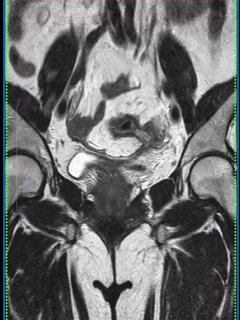

14 окт 2024

У пожилого мужчины после переохлаждения резко появилась задержка мочеиспускание, урологи утверждают, что у него – острый простатит. А на Магните – типичный рак, по крайней мере, PI-RADS 5.

Как считаете, может ли острый простатит выглядеть вот так? Асимметричный, с достаточно чётким контуром, да ещё и с быстрым накоплением контраста и быстрым же его вымыванием?

Что-то я сильно сомневаюсь, поделитесь опытом.